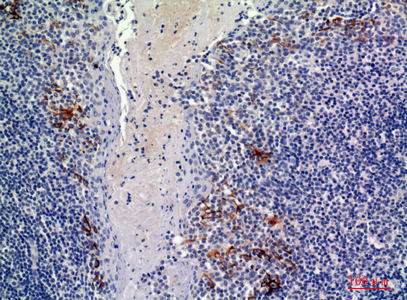

WB,FC,IHC-P,IF-P,IF-F,ICC/IF,ELISA

稀释比(Dilution Ratio)

WB 1:500-2000, Flow Cyt 1:50-200, IHC-P 1:100-500, IF-P/IF-F/ICC/IF(paraffin section), ELISA 1:5000-20000